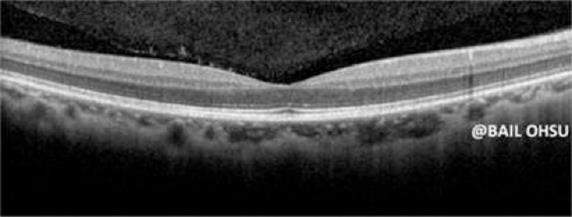

In vivo OCT imaging of Retina and Choroid

Ultrahigh speed SDOCT (500,000 A-scans per second) provides ability for comprehensive assessment of the retina status over a large field view. (a) 3D rendered volumetric image. (b) to (f) are typical depth resolved fundus (en-face) images, which are corresponding to the depth positions marked by the red, yellow, green, blue and purple lines in (a).